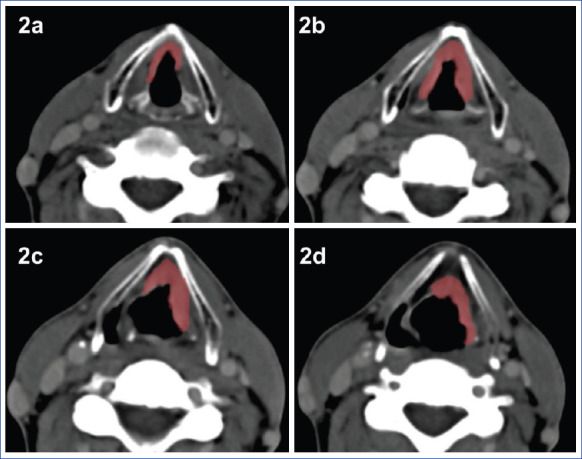

研究目的在这项回顾性研究中,我们评估了肿瘤体积、分级侵犯深度在预测颈淋巴结转移中的有效性:方法: 对接受手术的177例喉鳞癌患者进行回顾性评估。分析了患者的年龄、性别、肿瘤-结节-转移(TNM)分期、分级、浸润深度和计算机断层扫描(CT)肿瘤体积。结果:32名患者(29.91%)的宫颈淋巴结呈阳性。13例(46.43%)分化较差的肿瘤和19例(24.05%)分化中等的肿瘤发现了淋巴结转移。淋巴结阴性患者的平均体积为(2.15±0.14)毫升,淋巴结阳性患者的平均体积为(2.97±1.05)毫升。淋巴结阴性患者的平均浸润深度为(10.1±0.87)毫米,淋巴结阳性患者的平均浸润深度为(11.3±1.05)毫米。肿瘤分级和体积可成功预测喉鳞状细胞癌患者的淋巴结转移,但浸润深度与淋巴结转移无关(分别为P=0.047、P=0.0022、P=0.916):结论:肿瘤分级和体积可预测喉鳞状细胞癌患者的颈淋巴结转移,而浸润深度则无法预测。通过放射学方法计算肿瘤体积有助于预测淋巴结转移,从而最大限度地减少浸润深度等测量数据的可变性。

Results: Thirty two patients (29.91%) had positive cervical lymph nodes. Lymph node metastasis is detected in 13 (46.43%) poorly differentiated tumors, and in 19 (24.05%) moderate-well differentiated tumors. Mean volume was 2.15±0.14 cc in lymph node negative patients and 2.97±1.05 cc in lymph node positive patients. Mean invasion depth was 10.1±0.87 mm in lymph node negative patients and in 11.3±1.05 mm lymph node positive patients. The tumor grade and volume predicted successfully lymph node metastasis in patients with squamous cell carcinoma of the larynx, however invasion depth was not associated with nodal metastasis (p=0.047, p=0.0022, p=0.916, respectively).

Conclusion: The tumor grade and volume could predict cervical lymph node metastasis in patients with squamous cell carcinoma of the larynx, whereas the depth of invasion did not. Calculation of the tumor volume radiologically can help predict lymph node metastasis by minimizing the variability in measurements such as the depth of invasion.